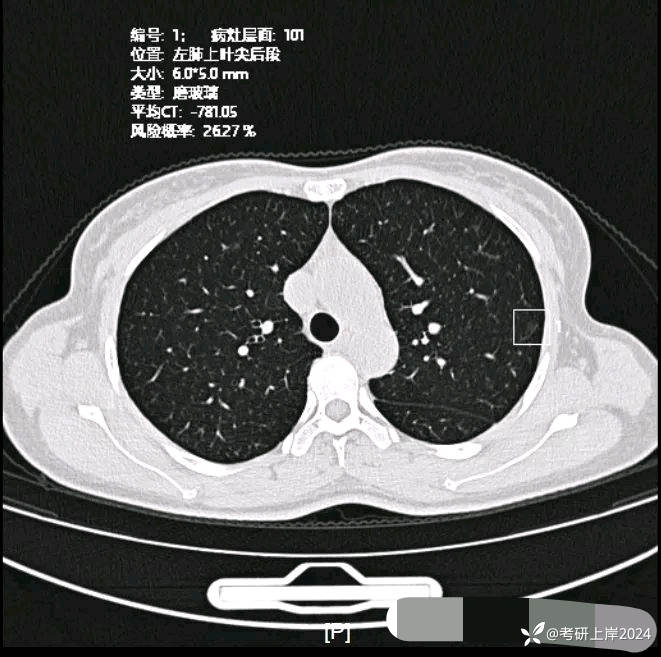

患者最近的检查有AI辅助诊断意见,找出的病灶分别如下:

病灶6:左上叶微小磨玻璃结节,轮廓较清,考虑肺泡上皮增生可能性较大;

病灶7:左上叶微小淡磨玻璃结节,考虑少许慢性炎或伴肺泡上皮增生可能性较大;

病灶9:右上叶磨玻璃结节,轮廓较清,密度稍均,似有微小血管贴边,考虑慢性炎伴肺泡上皮增生可能性较大;

病灶10:左上叶极淡密度的小片状模糊影,少许纤维增生或肺泡上皮增生;

病灶15:左上叶微小磨玻璃结节,轮廓较清,紧贴叶间裂,考虑肺泡上皮增生可能性较大;